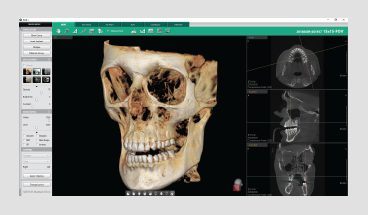

Powered by a new 3D VR graphics engine, the Ez3D-i is the ideal tool to effortlessly obtain the correct perspectives needed for accurate and true-to-measurement diagnosis.

• Easily navigate and obtain a sectional view by utilizing our new and intuitive 3D panoramic navigation mode

• Simply click and drag our viewing window over the 3D panorama to obtain a sectional view of that region

• Angulation made easy

By clicking 3D Navigator and positioning to ROI,

it’s easy to verify 2D sectional images.

• Available in all viewing modes in the Ez3D-i (MPR/Section/3DPan)